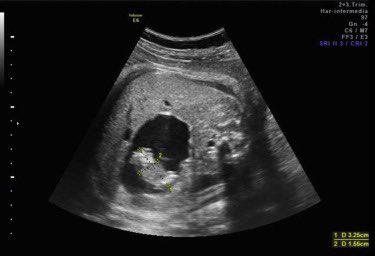

اشتبه الأطباء في أن بطنه المتضخم كان ورما. كان ذلك حتى فتحوه ووجدوا أنه كان يحمل التوأم الذي استوعبه في الرحم لمدة 36 عاما.

هذه حالة نادرة حقا تسمى الجنين في الجنين، حيث تم امتصاص توأم واحد، ولكنها لا تزال تعاني من إمدادات الدم والتغذية لدى المضيف.

لذلك استمر الجنين في نمو الأسنان والشعر وحتى الأعضاء التناسلية.